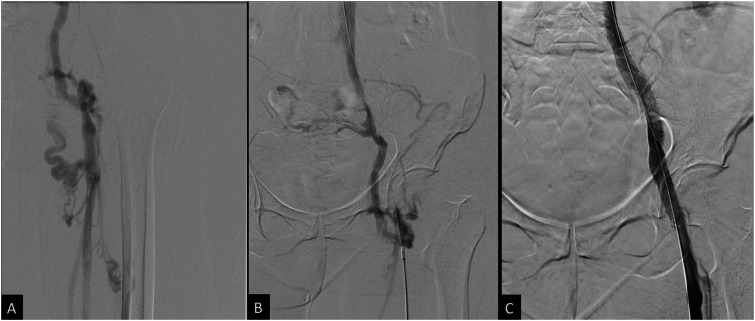

回腔静脉血栓形成和流出梗阻是一种有许多可能原因的疾病,通常表现为与静脉充血或不全有关的症状。最近的设备发展和血管内支架置入术和静脉成形术对生活方式限制症状的可用性难以保守治疗,导致对这些手术的兴趣增加。虽然静脉支架置入的几种常见并发症已经有了很好的描述,但一种罕见和紧急的并发症是附近动脉压迫或闭塞。在此,我们报告2例髂静脉再通和支架置入后发生髂动脉闭塞的病例,并讨论可能导致这种罕见并发症的因素。

Ileocaval venous thrombosis and outflow obstruction is a condition with many possible causes that typically presents with symptoms related to venous congestion or insufficiency. Recent device development and availability of endovascular stenting and venoplasty for lifestyle-limiting symptoms refractory to conservative management has led to increased interest in these procedures. While several common complications of venous stent placement have been well-described, 1 uncommon and emergent complication is nearby arterial compression or occlusion. Here we present 2 cases of iliac artery occlusion occurring after iliac venous recanalization and stenting, and discuss possible factors that may contribute to this uncommon complication.